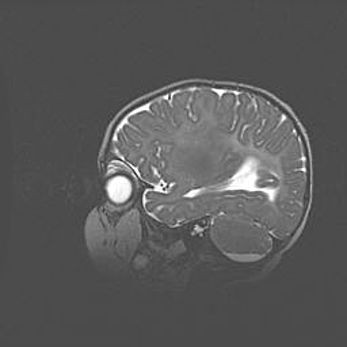

Множественные кисты обоих полушарий головного мозга, наибольшая из них в правой затылочной области. Ассиметричная атрофическая гидроцефалия.

Возраст: 7 месяцев

Вес: 5660 г

Пол: мужской

Окружность головы: 41,5 см

Срок гестации: 28-29 недель

Кисты головного мозга развиваются в результате многоочаговых некрозов вещества мозга и возникают вследствие перенесенной перинатальной инфекции, менингитов, энцефалитов, асфиксии, родовой травмы, расстройств мозгового кровообращения различного генеза. Образованию кист в веществе головного мозга плодов и новорожденных способствуют такие факторы, как высокое содержание в нем воды, недостаточная (или отсутствие) миелинизация и слабая астроглиальная реакция на повреждение.

Кисты могут сочетаться с гидроцефалией и другими поражениями головного мозга.